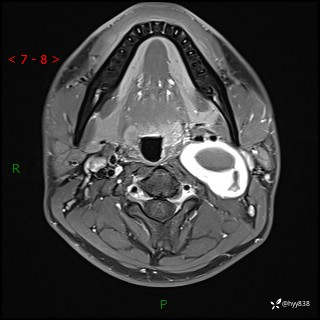

现病史:患者约3年前因感冒发现左侧颈部长一肿物,约半个鸡蛋大小,无明显疼痛及其他不适,一直未行特殊处理。3个月前发现左侧颈部肿物变大,随后至当地市第二人民医院耳鼻喉科行左侧颈部彩超示:左侧颈部囊实混合性包块;喉部MPR示:左侧胸锁乳突肌内前方占位,累及左侧喉旁间隙,建议增强扫描。建议手术治疗。患者考虑。随后至我院肿瘤科就诊,行细胞学穿刺示:考虑血管源性肿瘤可能,建议进一步检查。建议至我院口腔科就诊,行颌面部MRI示:左侧颌下腺后方团状异常信号灶,建议增强。建议手术治疗。为求进一步治疗,门诊以“左侧颈部肿物”收入院。 起病以来,患者神志清、精神良好,饮食睡眠良好,大小便正常,体重未见明显变化。

颈部MRI平扫+增强